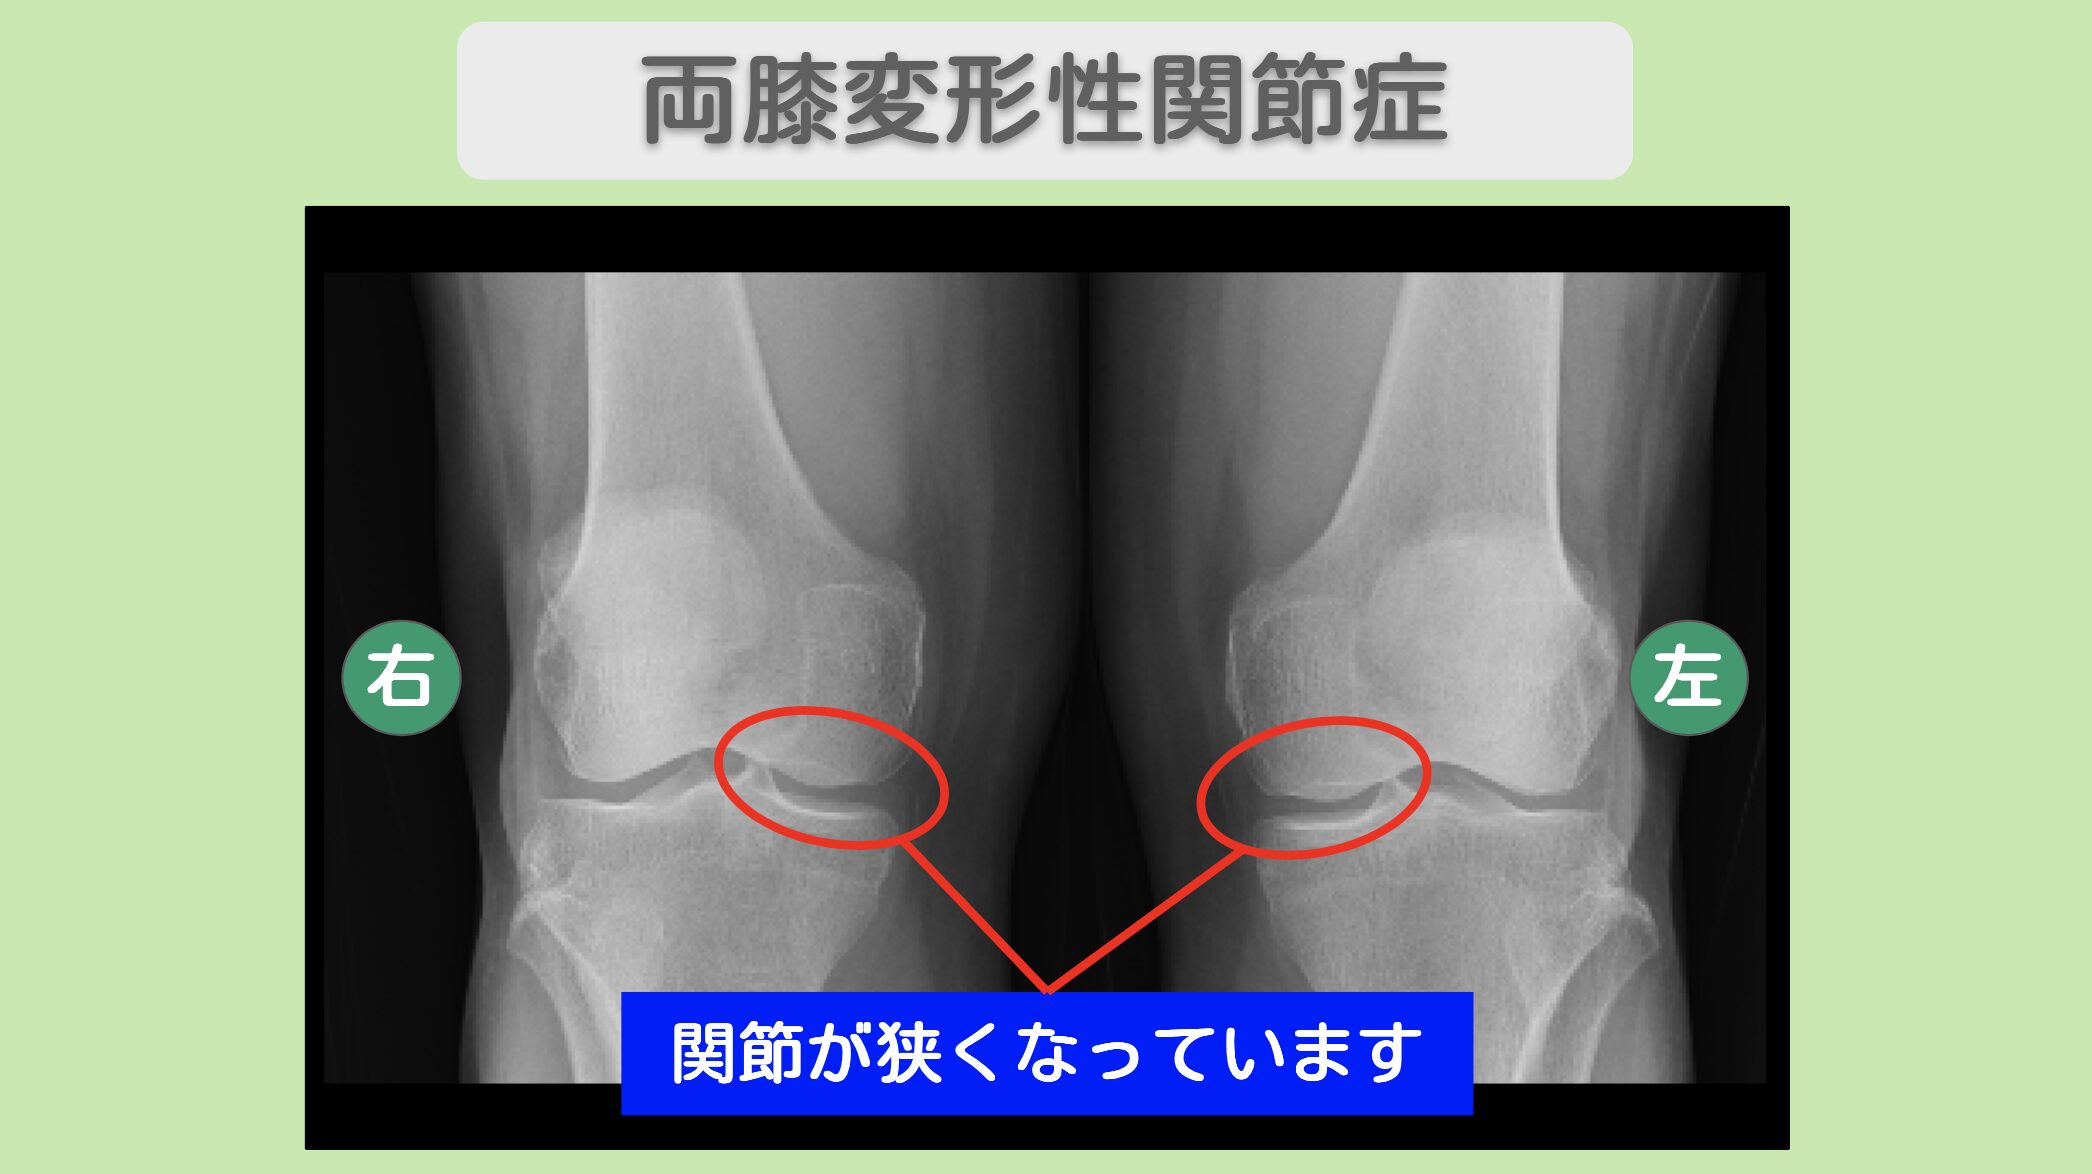

レントゲン所見

レントゲンにて両膝関節の狭小化を認めます。両手CM関節の狭小化を認めます。